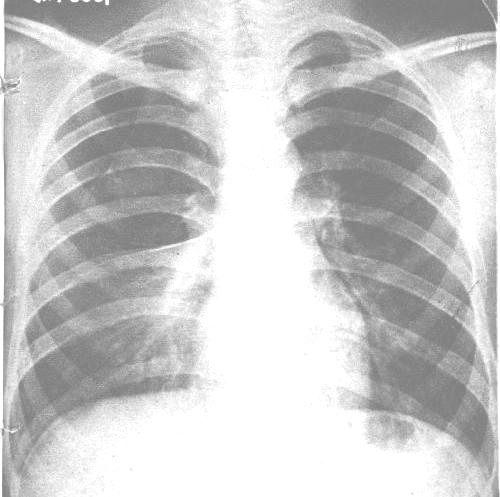

1.原发性气胸 又称特发性气胸。它是指肺部常规X线检查未能发现明显病变的健康者所发生的气胸,好发于青年人,特别是男性瘦长者。根据国外文献报道,这种气胸占自发性气胸首位,而国内则以继发性气胸为主。

有些学者根据肺大疱或合并自发性气胸患者作开胸手术及组织学检查,将肺大疱分成3型:Ⅰ型:为薄壁囊肿,与支气管几乎不相通,基本属于肺外性质,单腔、腔内无小梁,直径一般为数厘米,有时可达15~25cm,普通X线胸片上显而易见。并形成张力性大泡性肺气肿。对本型作手术切除大泡,治疗效果最好。Ⅱ型:大泡为中等直径大小,纤维化厚壁,位于肺实质深部,属于肺内大泡。大泡内被许多间隔分开。胸腔镜下仅可见其表面部分。一叶肺内可见数个Ⅱ型肺大疱。患者可无症状。X线胸片亦可无表现。但大泡破裂时即引起自发性气胸。破裂的大泡在胸腔镜下一般可窥见。Ⅲ型:为大的肺大疱,且不只存在于一个肺叶内,泡内具有多个小梁,并与支气管广泛交通。本型是弥漫性大泡性肺气肿最常见的原因,一旦破裂即形成自发性气胸,本型发病率和死亡率均高。